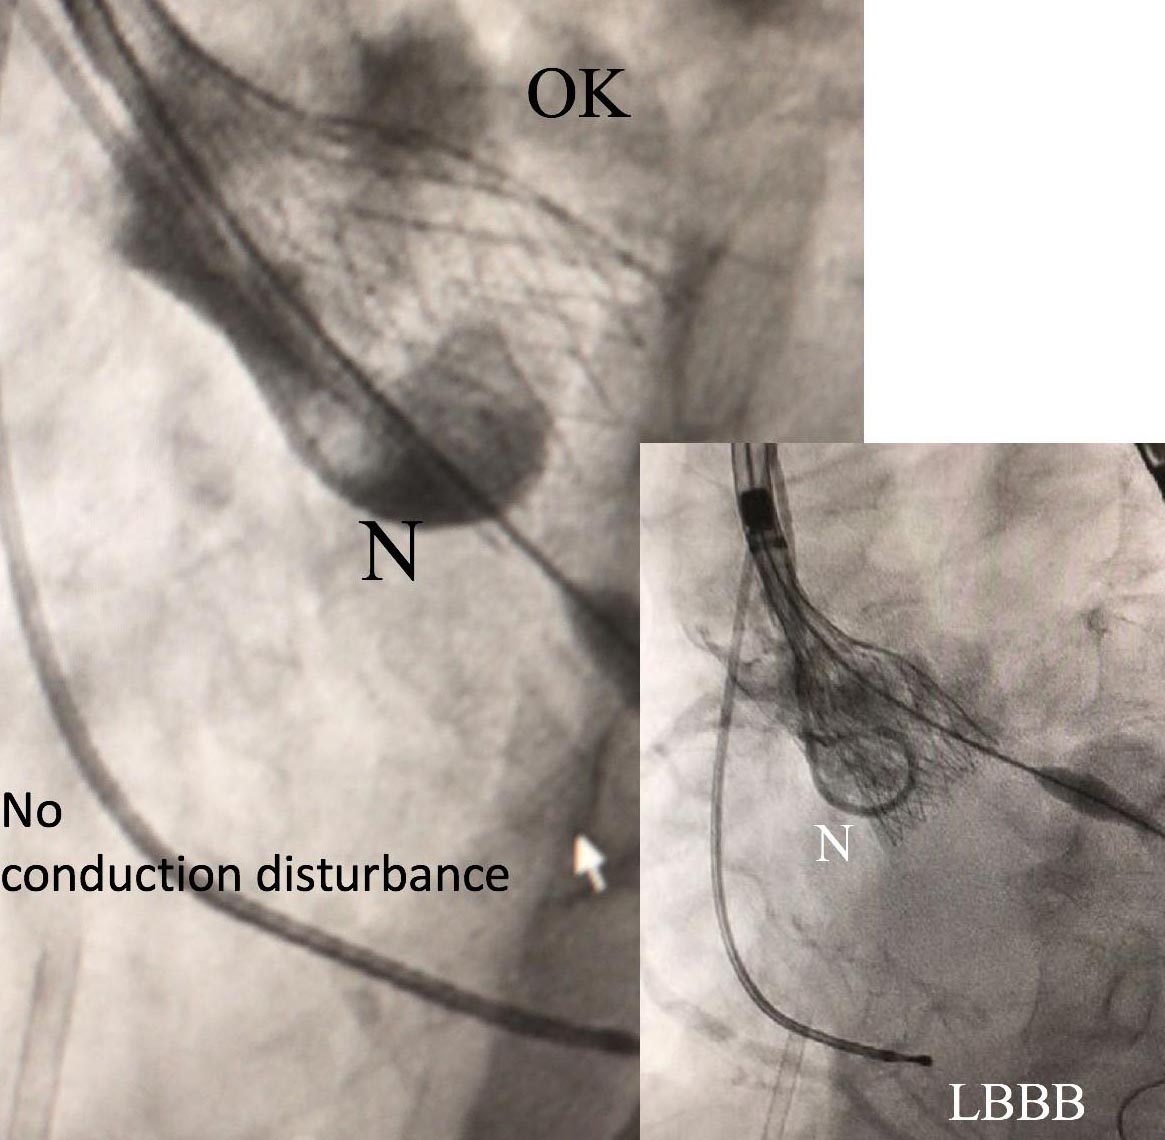

TAVI後の合併症として伝導障害は頻度の高いものであり、その中でも左脚ブロックが最も多いとされています。(参考文献①)これは伝導路の解剖学的特性に起因します。右房にある房室結節から連なるHis束が膜性中隔を通り左側へと走り、膜性中隔と筋性中隔の間に出てきます。ここで左脚に分枝しますが、ここは大動脈無冠尖と右冠尖の間の基部と非常に近いところにあります。TAVI弁による圧迫によって、この伝導路に様々な程度で機械的な障害が起こり、伝導障害が発生します。また、この伝導路には個人差があることが知られており、膜性中隔が短い患者さんでは伝導障害がより発生しやすいとされています。(参考文献②)

術前の造影CT検査をもとに、複数の医師で大動脈弁輪部の計測を行い、適したTAVI弁の種類およびサイズを決定しています。また、左脚ブロックはTAVI弁の留置位置が深いと生じやすいことが知られていますので、位置が深くなりすぎないように、術中の大動脈造影および経食道心エコーを確認して位置決定を行っています。